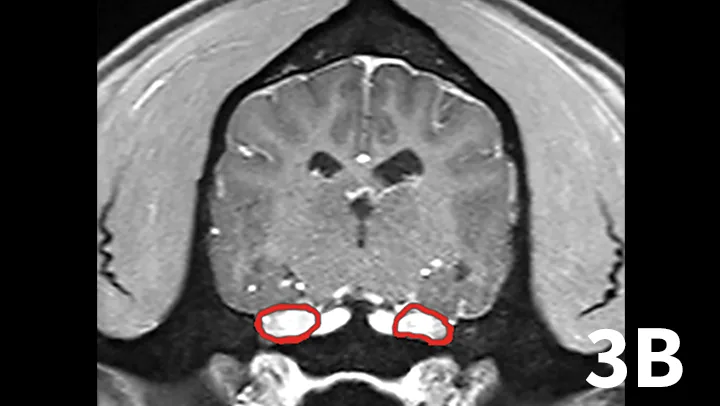

Nerve sheath tumors (NSTs) are perhaps the most common cause of chronic, progressive peripheral cranial nerve disease in older dogs. They arise from Schwann cells or pericytes, are typically slow growing, and are invasive to surrounding nervous system tissue. Metastasis is a rare event associated with NSTs. Whereas they most commonly affect the brachial plexus and lumbosacral plexus, NSTs also can arise within cranial nerves, with the trigeminal nerve most frequently affected. Clinical signs of trigeminal NSTs are ipsilateral to the NST and include unilateral masticatory muscle atrophy, facial hypalgesia, reduced corneal sensation, and Horner syndrome.1 Magnetic resonance imaging (MRI) is the modality of choice for identifying lesions. On MRI, NSTs are mass-like, tubular structures that are contiguous with a nerve (Figure 1).2 Lesions are often hyperintense (bright) on T2-weighted images (T2WIs), indicating high water content from edema, neoplastic cells, or inflammation, and strongly contrast enhance on T1-weighted images (T1WIs) following the delivery of gadolinium, suggesting a blood–nerve barrier breakdown or neoangiogenesis.

Transverse T2WI (A) and postcontrast T1WI (B) from a 10-year-old golden retriever with a 6-month history of left masticatory muscle atrophy. Adjacent to the left lateral pons is a mass-like lesion (arrow) confluent with the left trigeminal nerve that is T2-hyperintense and contrast-enhances on T1WI. There is profound atrophy of the left temporalis muscle (arrowheads), which is likewise T2-hyperintense with subtle contrast enhancement on T1WI. These findings are consistent with a nerve sheath tumor of the proximal trigeminal nerve with secondary neurogenic muscle atrophy.